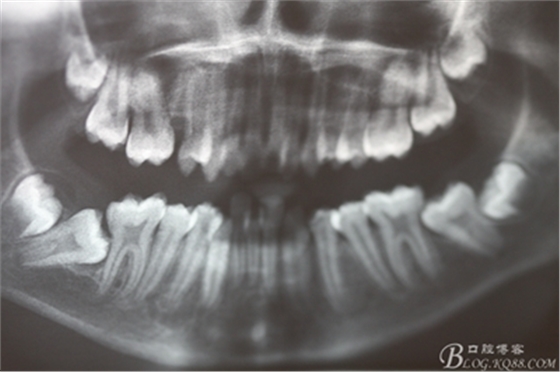

圖3. 這是患者的全景片影像檢查:看不清16與14之間是否有牙根遺留